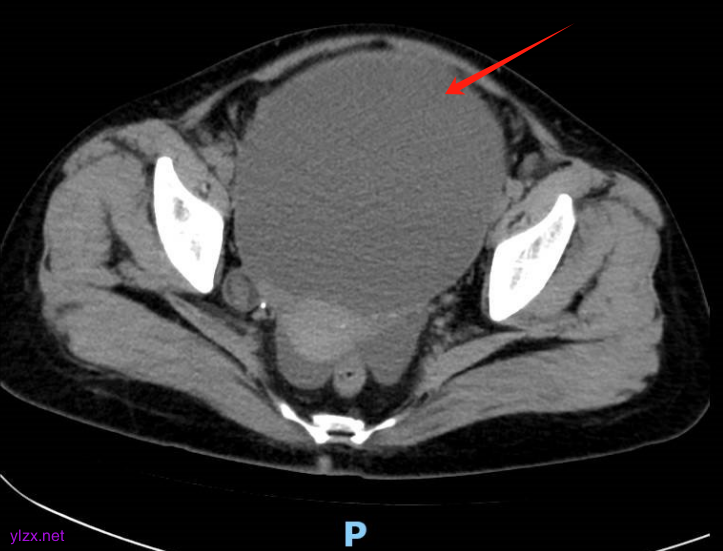

下腹部CT平扫(图1):下腹腔-盆腔见巨大囊状低密度影,其内密度不均匀。右下腹部部分肠管扩张、积液、积气,双侧输尿管腹段未见扩张。下腹腔、腹膜后未见肿大淋巴结,下腹腔积液。

图1 下腹部CT平扫示下腹腔-盆腔见巨大囊状低密度影,其内密度不均匀。